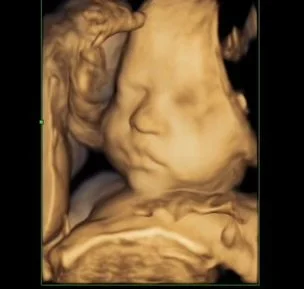

I got to see a 3D Sonogram of my baby’s face yesterday during Heather’s appointment. That was super cool and makes it feel a little more real. He’ll be here before we know it!